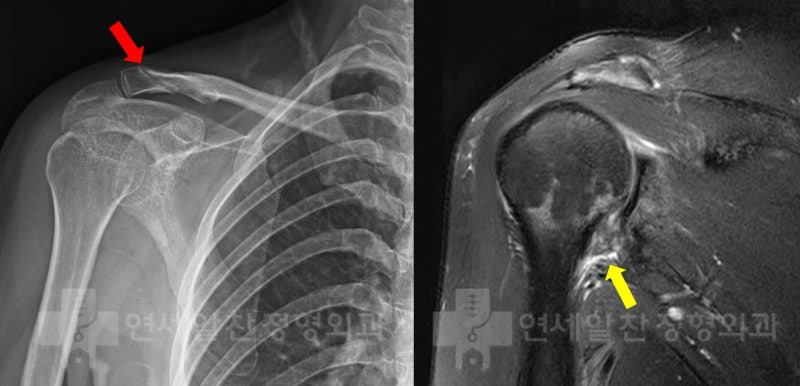

38세 여자 환자로 3개월전 쇄골 골절 진단 받은 후 velpeau bandage 를 하여 보전적 치료를 한 후 골절 유합은 되었으나 관절 가동범위 제한이 심하고 통증이 심하여 본원으로 내원하였다. 환자는 외국에서 거주하고 있는 환자로 MRI 검사까지 진행하였고 조금 더 정확한 진단과 치료를 위해 본원으로 내원하에 되었다고 하였다. 이학적 검사상 Forward Flexion ( 60 /150) Abduction ( 60 /150) I/R ( 20 /40) E/R ( 40 /90) 로 가동범위의 제한이 심하였다.

골절이 유합된 상태로 외상(골절)후 장기간 고정에 의한 유착성 관절낭염 진단하에 관절수액팽창술(hydro-dilatation) 및 재활치료를 권고하였다.